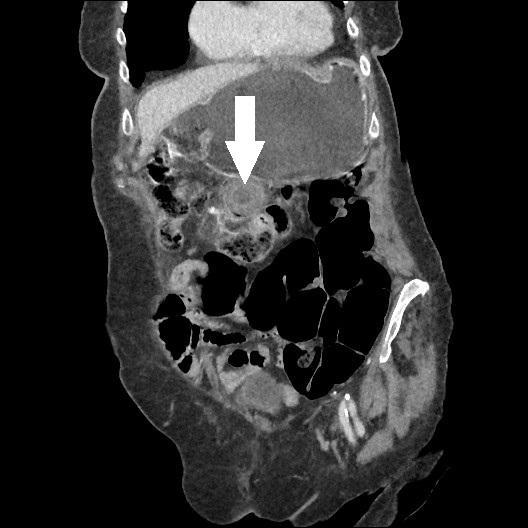

A. Miros, A. Paśnikowska, M. Romanowska, Zespół Barnarda jako rzadka przyczyna niedrożności jelita cienkiego... 53

ści o opisywanej etiologii, zwłaszcza gdy chorym jest osoba w wieku podeszłym. Postawienie szybkiego rozpoznania bywa utrudnione ze względu na często współwystępujący z wiekiem zespół otępienny, który uniemożliwia zebranie wywiadu. Istotną rolę w diagnostyce odgrywają badania RTG oraz TK. Istnieje wiele możliwości terapeutycznych, jednak zawsze należy spośród nich wybrać tę najbardziej optymalną i bezpieczną dla pacjenta, nie siląc się na jednoczasowe, duże operacje odtwórcze. W sytuacjach takich jak opisana ryzyko powikłań związanych z wykonaniem obciążającej i rozległej operacji może przeważać nad przewidywaną korzyścią z zabiegu.

Piśmiennictwo

1. Halabi W.J., Kang C.Y., Ketana N. et al.: Surgery for gallstone ileus: a nationwide comparison of trends and outcomes. Ann Surg 2014; 259(2): 329-335.

2. Tsang C.F.: A rare case of gallstone ileus – the unanswered question. J Surg Case Rep 2021; 2021(4): rjab164.

3. Lourenço S., Pereira A.M., Reis J. et al.: Gallstone ileus: an improbable cause of mechanical small bowel obstruction. Cureus 2020; 12(11): e11460.